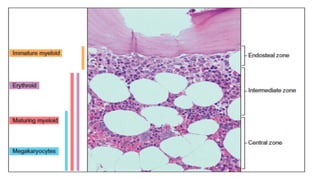

Cellular organization:

• In MDS, there is disorganization of hematopoiesis:

oImmature myeloid elements occur away from bone trabeculae.

oErythroid elements fail to form well-defined clusters.

oMegakaryocytes may cluster.